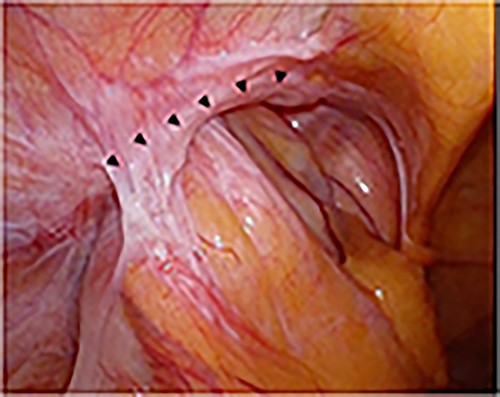

Intraoperative findings of right inguinal region after peritoneal incision; the black triangles show the hernial orifice; the dotted circle indicates the assumed hernia sac; the black cross indicates the internal inguinal ring (A); by pressing the inguinal region from the body surface, intermuscular soft tissue was prolapsed into the abdominal cavity (B).

A laparoscope was inserted through a 12-mm umbilical port. Another 12-mm port was created at the level of the umbilicus aligning with the right mid-clavicle, and a 5-mm port was placed on the contralateral side of the line connecting the hernial orifice to the umbilicus. The bulging in the abdominal cavity caused by the hernia’s content could be observed in the laparoscopic view (Fig. 3A). Laparoscopic reduction was successfully performed, and a small segment of the incarcerated bowel was mildly erythematous. Therefore, we decided that bowel resection was unnecessary. After observing the hernial orifice, we found that the peritoneum with the right medial umbilical fold was easily turned inward into the abdominal cavity, suggesting a type of sliding hernia involving the medial umbilical folds [7], and the hernial orifice could not be identified (Fig. 3B). After the peritoneal incision and dissection, the hernial orifice was found lateral to the right epigastric artery. However, although the inner inguinal ring was small, the hernial orifice was observed under the transversus aponeurotic arch in the ventral–lateral direction (Fig. 4A). By pressing the inguinal region from the body surface, the hernial orifice could be recognized more easily (Fig. 4B). The size of the hernial orifice was ~20 mm. Based on the aforementioned findings, the patient was rediagnosed with right interparietal inguinal hernia. After diagnosis, laparoscopic preperitoneal hernia repair was performed with a mesh using the same surgical procedure as that for a standard transabdominal preperitoneal (TAPP) repair. In addition, the edge of mesh was placed ≥3 cm from the hernial orifice, and the center of the mesh was slightly ventral and lateral to the internal inguinal ring.